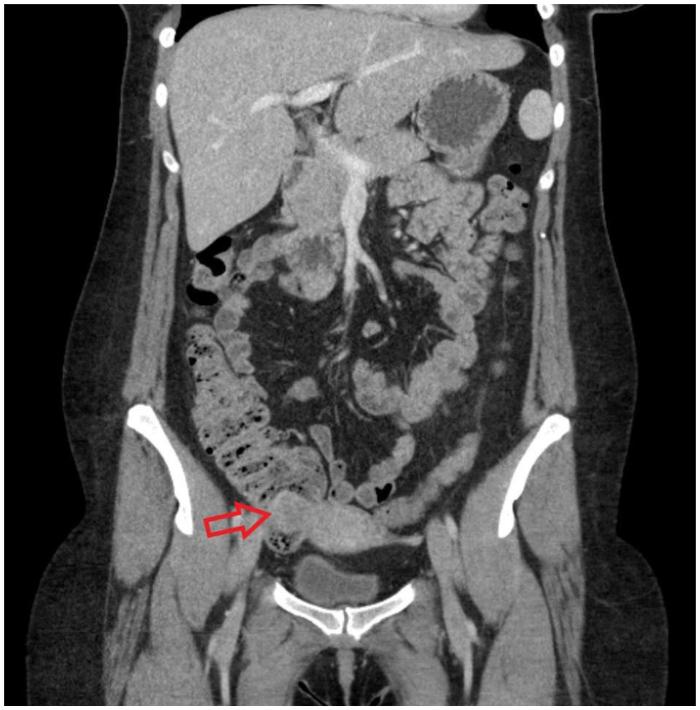

CASE

A 35-year-old woman, gravida 4, para 1, at 37 weeks and 3 days of gestation, without a known history of endometriosis but with two prior miscarriages, presented with severe anemia and intrauterine fetal demise. During delivery, melanotic stool was noted. Colonoscopic biopsy noted the source of bleeding to be a 2 cm endometriotic implant in the patient's cecum. Suppression therapy was started. Postpartum, the patient underwent laparoscopic cecectomy and pathology confirmed the diagnosis of endometriosis.

病例

一名35岁女性,孕4产1,妊娠37周零3天,既往无子宫内膜异位症病史,但有两次流产史,因严重贫血和宫内胎儿死亡就诊。分娩期间,发现有黑色粪便。结肠镜活检显示出血源为患者盲肠内一个2厘米的子宫内膜异位植入物。开始进行抑制治疗。产后,患者接受了腹腔镜盲肠切除术,病理证实为子宫内膜异位症。